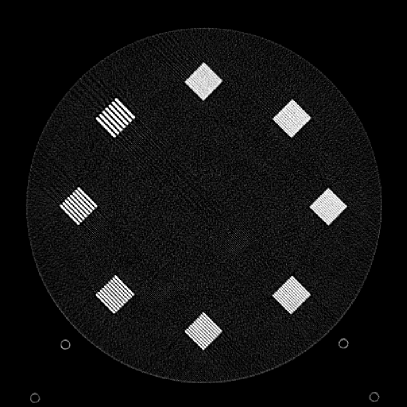

To evaluate image quality, we first tested the performance of JENG on a standard CT phantom, CT ACR 464 phantom 35. Then we tested JENG on 5 clinical thoracic datasets and 3 abdominal datasets. The ACR 464 phantom contains four modules in total, with each module 40 mm in depth and 200 mm in diameter. The first module has 4 different inserts to test CT number fidelity. In addition, the module contains a series of wires for cross-plane resolution evaluation, shown as white horizontal bars near the center in Fig. 9(a), and are visible in 0.5 mm z-axis increments. The second module tests low contrast resolution, but is not used in this paper. The third module, shown in Fig. 9(b), is a uniform cylinder of water-equivalent material of 0 Hounsfield units (HU), and we used this module to quantitatively measure image noise profile and in-plane resolution. The fourth module consists of resolution bars of various spatial frequencies for analysis on high contrast resolution. To scan the phantom, the scanner setup used dual sources with 2 focal spots at each source. In addition, the projections were acquired using the same protocol for clinical thoracic scans with 100 KV, a nominal tube current of 718 mA and a high helical pitch of 2.8. For all experiments, we compared JENG against the state-of-the-art Siemens ADMIRE, reconstructed with a BL-64 soft tissue sharp kernel, and we define ADMIRE as the clinical standard hybrid IR method for the rest of the paper.

Figure 10: Clinical Standard hybrid IR vs JENG performance, with a display window center of 650 HU and a window width of 1500 HU. The spatial frequencies for bar patterns from top going clock-wise are 1.2, 1.0, 0.9, 0.8, 0.7, 0.6, 0.5, 0.4 mm-1. (a) The clinical Standard hybrid IR at L1 denoising strength using a soft tissue high contrast kernel. Note that significant aliasing streaking artifacts are present near the bar patterns. (b) JENG at a comparable L1 noise level but with much clearer bar pattern and fewer artifacts than the clinical standard hybrid IR. (c) The clinical standard hybrid IR at a stronger denoising strength of L3. (d) JENG at a comparable L3 noise level.

The first experiment we performed was a visual comparison of in-plane spatial resolution between JENG and the clinical standard hybrid IR. We used the ACR phantom module 4 for this evaluation, which has 8 resolution bars of various spatial frequencies from 0.4 mm-1 to 1.2 mm-1. To obtain a fair comparison, we matched the image noise variance in the uniform regions of JENG and the clinical standard hybrid IR and studied their in-plane spatial resolution and undersampling streaking artifacts. In addition, we performed two sets of experiments. The first set of experiments matched their image noise variance at the L1 denoising strength of the clinical standard method with a noise variance of 33926 in the uniform regions. The second set of experiments matched their image noise variance at stronger L3 denoising strength of the clinical standard method with a noise variance of 12988 in the uniform regions.

Fig. 10 is an example image for resolution bars and the spatial frequencies for the bar patterns from top going clockwise are 1.2, 1.0, 0.9, 0.8, 0.7, 0.6, 0.5 and 0.4 mm-1. Fig. 10(a) is the resolution bars reconstructed by the clinical standard hybrid IR at L1 denoising strength. Fig. 10(b) is JENG reconstructed at an image noise variance comparable to the L1 denoising. Fig. 10(c) is the clinical standard hybrid IR at a stronger L3 denoising strength and we can observe that the result at L3 denoising leads to less image noise than the result at L1 denoising in Fig. 10(a). Fig. 10(d) is JENG at an image noise variance comparable to the L3 denoising. To help readers better see the image quality difference between the clinical standard hybrid IR and JENG, Fig. 11 is the difference image between the two algorithms at L1 denoising. A noticeable difference between the clinical standard hybrid IR and JENG is that the clinical standard method in Figs. 10(a) and (c) have strong undersampling aliasing artifacts near the phantom periphery, which show a pattern of high density streakings and the streakings point along the direction of X-rays. In addition, the magnified sub-figures show that the bar pattern at 0.8 cycles/mm is unresolved with blurry details. In contrast, JENG in Figs. 10(b) and (d) effectively decimates the undersampling artifacts and the bar pattern in the magnified sub-figures of JENG is completely resolved with clearer details.